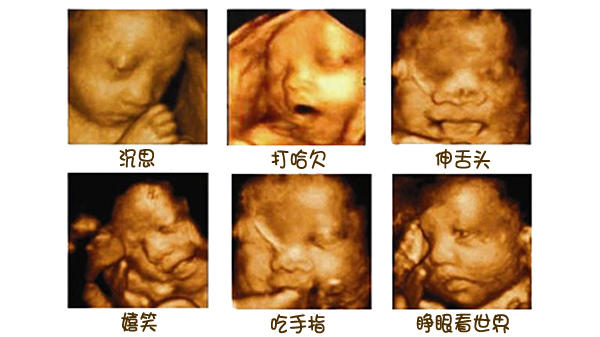

3、 胎儿时常在子宫内活动

从第四个月开始,孕妈妈能感受到一定胎动,说明胎儿有生命体征了。等到28周,胎儿的四肢和面部已经逐渐趋于完善,能蹦能动了。若是个调皮外向的胎宝宝,甚至会在妈妈子宫内打拳呢。

所以,在探头勘测超声波影像时,胎儿在动。加上胎儿整个是泡在羊水里面,左动一下,右动一下,拍摄出来的成像难免会失真。